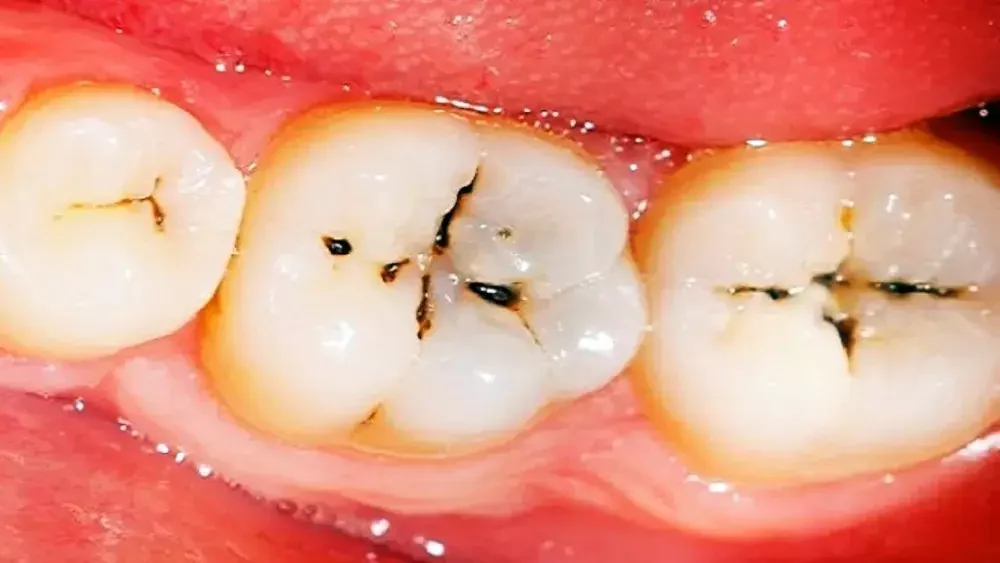

3. Lubang atau Perubahan Warna pada Gigi

Pada beberapa kasus, Anda dapat melihat langsung adanya lubang kecil atau perubahan warna pada gigi geraham, seperti bercak cokelat, hitam, atau putih kusam. Perubahan ini menandakan adanya kerusakan pada struktur gigi.